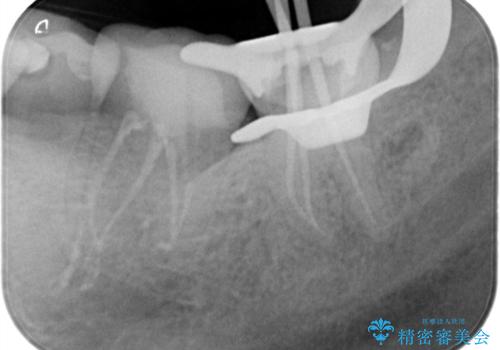

レントゲンや口腔内所見にて以下のような説明ののち、患者様が保存を希望されたため、当院では根管治療~オールセラミッククラウンにて修復処置を行いました。痛みも消えて、経過良好です。

病気の原因は細菌であるため、細菌数を減らすための処置として一般的に②根管治療という選択肢がある。再根管治療の場合は病気が治るのは7割ぐらいであり、それでも治らない場合は意図的再植術を行い9割近くまで成功率を高めることができる。ただし、今回のケースでは根尖が湾曲しているため意図的再植時の破折リスクが高いため適応は難しい。また、根尖の病変が治ったとしても、歯周病、カリエス、脱離や破折リスクがあり治療後抜歯になる可能性もある。治らない可能性や治療したとしても抜歯になる可能性があることを考慮し、③抜歯の選択肢をとる場合もある。